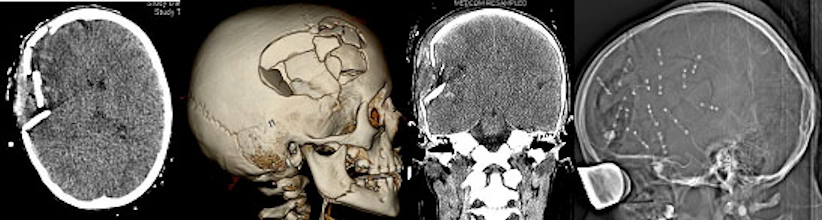

Rekonstruktive Indikationen bei Schädeltraumen sind häufig. Immerhin ca. 83.400 Kinder unter 15 Jahren werden jedes Jahr im Krankenhaus behandelt, davon haben 80% ein leichtes, 20% jedoch ein schweres SHT. Davon erleiden etwa 4% eine Schädelfraktur. Kommt es zu einer Impressionsfraktur muss manchmal eine Hebung oder Rekonstruktion der Kalotte erfolgen. In extremen Fällen (Abbildung 6 [Abb. 6]) benötigen auch einmal solche verletzten Kinder eine umfangreiche Rekonstruktion der Integrität ihrer Kalotte, häufig auch im Bereich der Frontobasis. Zur Rekonstruktion fehlender oder aus Gründen der Verletzung zu verwerfender Knochenanteile stehen dabei bei Kindern Split bone-Techniken zur Verfügung. Dabei wird die Kalotte in Lamina interna und externa getrennt und steht somit als autologes Präparat zur Verfügung (Abbildung 7 [Abb. 7]). Vor allem beim kindlichen, wachsenden Schädel bietet dies Vorteile. Alternativ kommen heute auch Fremdmaterialien, Titanmesh aber auch Custome bone-Verfahren zum Einsatz.

Abbildung 6: Offenes SHT mit Impressionsfraktur nach Misshandlung mit Hammerschlag, primäre Rekonstruktion und gutes neurologisches Outcome bei 10-jährigem Mädchen